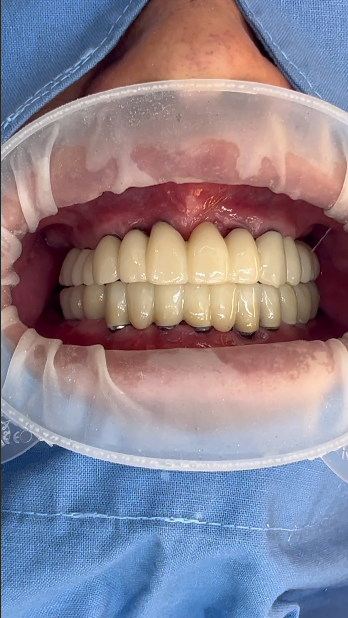

수술당일 임시치아,

4회 방문,4개월 전체임플란트

하지만 그런 걱정 하나하나를 잘 해결하고 나면 치료는 생각보다 간단하고 빨리 끝날 수 있답니다. 하루에치과에서는 이런 경우 발치와 동시에 전체임플란트를 식립하고 당일에 바로 치아를 만들어 드리기 때문에 치아없이 지내는 시간이 없어요. 오히려 치료전보다 예쁜 치아를 끼고 집에 가십니다. 그래서 이미 수술하는 날 만족도가 좋습니다.